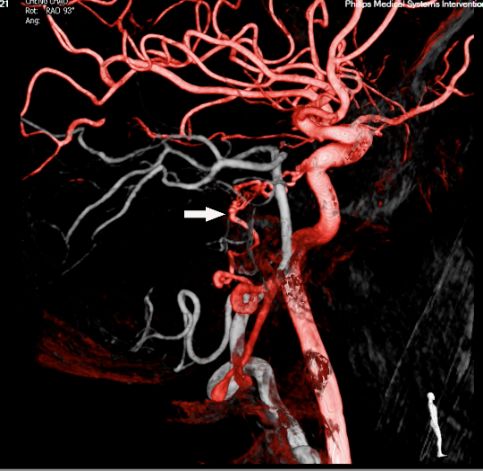

头颅MRA未见颅内异常血管,但头颅MRI-TOF像可见左侧天幕缘异常血管影(图2),CT薄层增强扫描见枕骨大孔区异常血管影(图3)。于2017年12月25日局麻下行全脑及全脊髓血管造影,脊髓血管造影未见异常,双侧椎动脉造影未见异常,最后行左侧颈内动脉造影示脑膜垂体干供血的天幕区硬脑膜动静脉瘘,瘘口位于岩骨中内1/3,直接经桥脑中脑侧静脉、扩张的延髓周围静脉向脊髓前静脉引流(图4)。造影诊断:左侧天幕区硬脑膜动静脉瘘。

图2. MRA未见异常,MRI-TOF示左侧天幕缘异常血管影(箭头所示)

图4. DSA血管造影